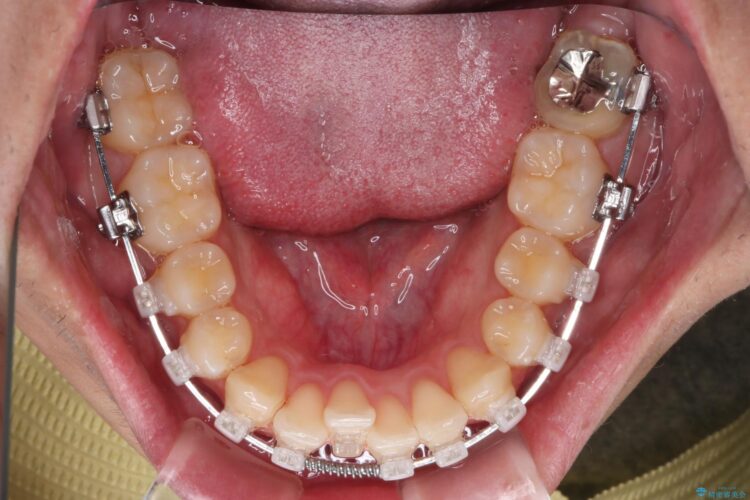

目立ちにくいクリア装置で八重歯とがたつきの改善

上の八重歯と下の歯のがたつきが気になるとご来院された患者様です。

精密検査の結果、抜歯の必要はないと判断しました。臼歯を遠心移動させ、歯列をワイヤーで整えることでスペースを確保し、IPR(歯と歯の間を削る処置)を加えて歯並びを綺麗にする治療計画を立てました。

歯の移動にオープンコイルとMI(歯肉に埋入するネジ)を用いました。